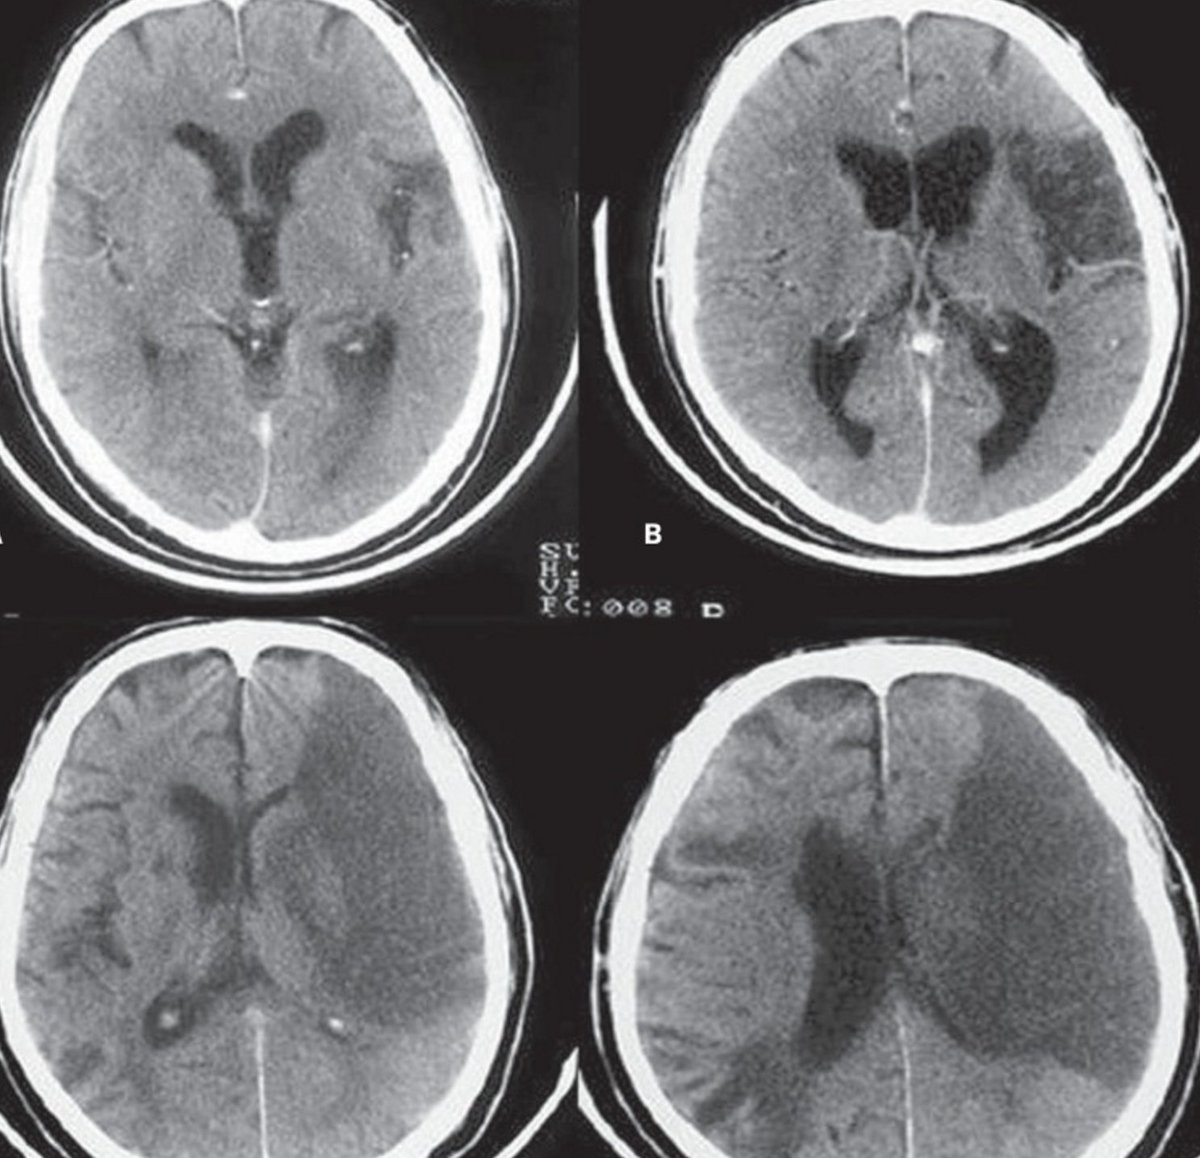

Stroke on my

Stroke on my 123 фотографий